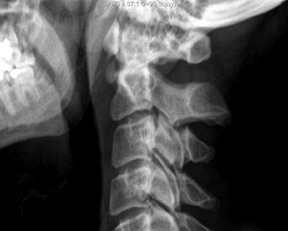

Calcifi cation just inferior to the anterior tubercle of C1.

The diagnosis can be established radiographically by identification of pathognomonic findings of amorphous calcification anterior to C1-2 with associated asymmetric soft-tissue swelling. All these finding can often be identified on plain films. However, calcification may not be evident on an initial plain radiograph; only diffuse soft-tissue swelling in the prevertebral C1-4 area may provide a clue for diagnosis. A CT scan can help identify calcific deposits, which can often appear faint on plain film. MRI is not typically necessary for this diagnosis.

The same principal radiographic findings of retropharyngeal calcific tendinitis hold true for plain films, CT and MRI: prevertebral soft-tissue swelling and amorphous calcification anterior to C1-C2. The diffuse, prevertebral soft-tissue thickening typically extends from C1 to C4. The soft-tissue thickening represents either discrete effusion or diffuse edema, which can be differentiated on CT or MRI. The lack of enhancement surrounding the effusion can be helpful in differentiating a reactive effusion from an abscess. Knowledge of this condition will save a patient from unnecessary treatment and undue anxiety.